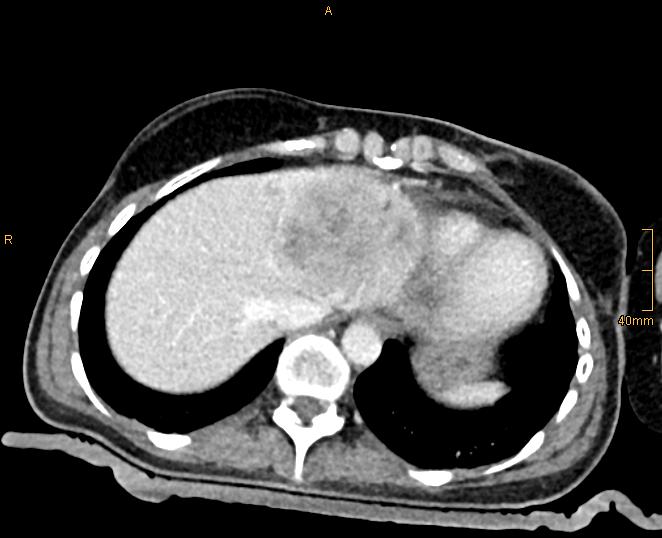

Figure 1A: Breast cancer liver metastasis with 9 cm in left liver lobe.

In the meantime, we have treated > 900 patients with > 3000 liver tumors in > 1500 sessions and collected them in our prospective SRFA registry. After bridging therapy with SRFA for liver transplantation, complete histopathological response was found in 183 of 188 treated lesions (97.3%) and in 50 of 52 lesions > 3cm (96.2%) 2. In a recent paper reporting the results after SRFA of very large tumors (> 8 cm) 3 (Figure 1) and in other studies including primary and secondary liver tumors the short- and long-term outcomes after SRFA were comparable to HR.